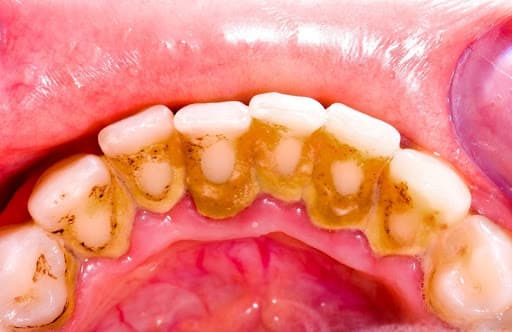

Nhiều bạn ngạc nhiên khi một ngày soi hàm răng trong gương phát hiện những mảng bám chân răng màu trắng, ngà vàng hoặc thậm chí màu nâu đã xuất hiện từ bao giờ. Những mảng bám đó chính là cao răng, hình thành từ chính những thức ăn còn đọng lại ở chân răng. Sau mỗi bữa ăn, các thức ăn này không được làm sạch dần bám chặt, lâu ngày, dưới tác động của vi khuẩn và các hợp chất muối vô cơ trong nước bọt dần cứng lại và bám chắc vào bề mặt răng hình thành cao răng.

– Mất thẩm mỹ cho răng: Quan sát lớp cao răng ngả vàng hoặc ngả nâu ở mặt trong của răng sẽ thấy được sự mất thẩm mỹ mà các lớp cao răng gây nên. Nếu không được khắc phục kịp thời, lớp cao này sẽ đóng dần về phía bề mặt ngoài của răng gây mất thẩm mĩ. Ngoài ra, càng nhiều cao răng, răng càng dễ bắt màu trong quá trình ăn uống bởi các cao răng thường có cấu trúc xốp, rỗng.

Cao răng nhiều gây viêm chân răng, tụt lợi và viêm nha chu